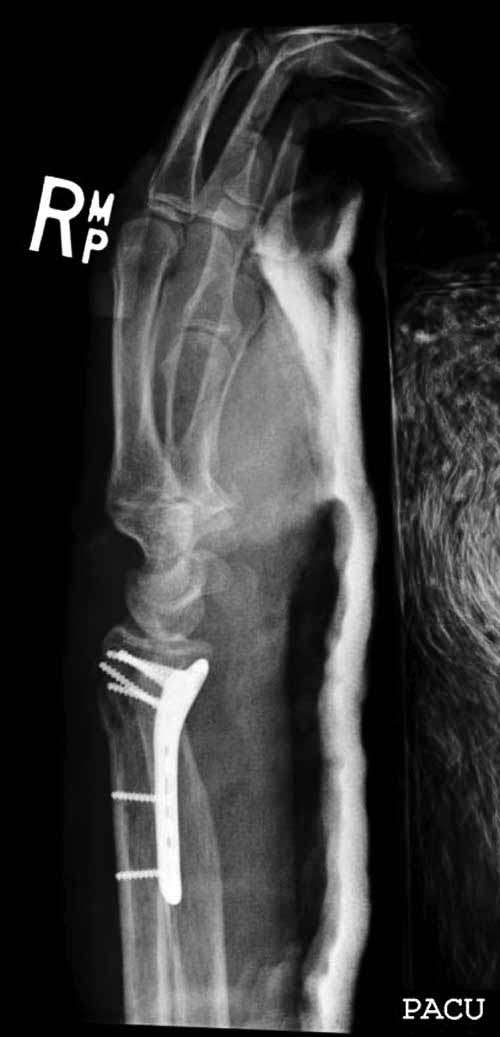

Сегодня все компании: Synthes, Stryker, Zimmer, Acumed, TriMed и т.д. имеют пластины для фиксации дистального перелома лучевой кости. На снимке метод фиксации дистальных переломов, справа Stryker, а слева пластина Synthes,

женщина 58 лет, политравма.

Нет не в вывихе, т. К. Из-за спицы проведенной через обе кости предплечья, то ротационные движения и подвижность локтевой кости резко ограничены, это может в некоторых проекциях расцениваться как подвывих, если найду покажу финальный снимок, там все рентгенологические показатели восстановлены.